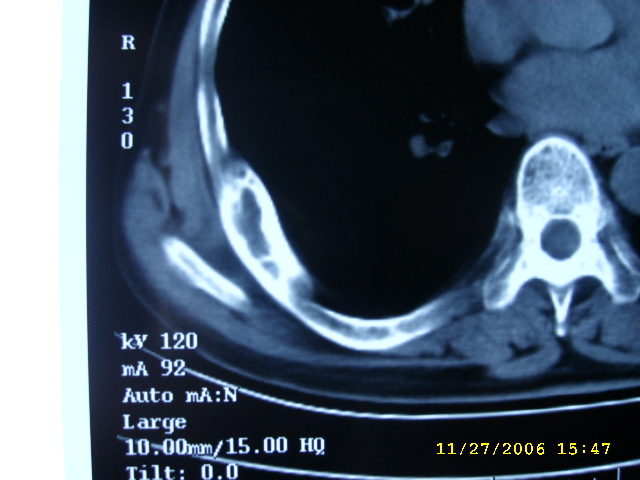

肋骨应该不是转移,其为膨胀性改变,边缘增厚硬化,临近软组织未见明显异常改变,考虑骨纤等病变。

肺部的病灶是比较肯定的,但肋骨骨质完整,未见破坏征象,故肋骨考虑骨纤维异常增殖症。

单纯肋骨局限性膨胀,边界清楚,皮质增生硬化,考虑:1  请详细了解病史,除外陈旧骨折.2 骨纤维异常增埴症

周围型肺癌.肋骨可能是陈旧骨折愈合.

右肺内病变考虑肺癌,右侧肋骨局部增粗,皮质增厚,髓腔增宽,有否陈旧骨折?先考虑骨纤维异常增殖症。

1.右下肺病灶周围型肺癌的可能性非常大。

2.右侧肋骨病变转移的可能性非常小,首先考虑骨母细瘤。次则考虑骨纤维异常增殖症。

建议详细询问病史,排除陈旧性骨折所致。